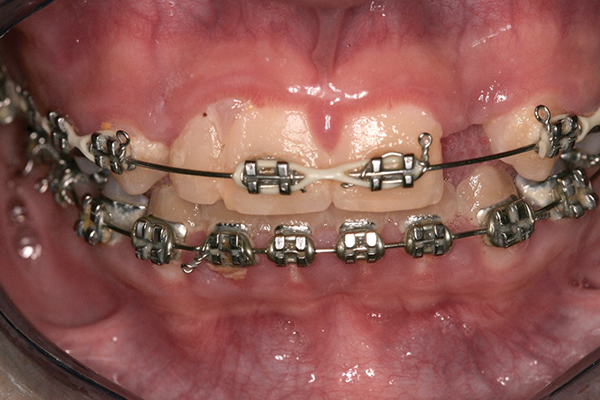

The patient saw her pediatric dentist for regular maintenance, returning to the orthodontist for yearly assessments until she reached the age of 12 years, 1 month, at which time orthodontic therapy commenced. Fixed edgewise orthodontic therapy was performed for 2 years and 7 months to create an ideal space for implant tooth No. 10, close the diastema between teeth Nos. 8 and 9, and coordinate the facial-to-maxillary dental midlines (Figure 6). When the appropriate coronal and apical mesial-distal space was created by the orthodontist for implant placement (age 14 years, 3 months), a resin-bonded retainer was fabricated for optimal stability of coronal and root position,29 and cemented with a resin cement (Figure 7 and Figure 8). Also, a conventional removable retainer was delivered.

Fig 6. Fixed edgewise orthodontic therapy.

Figure 6